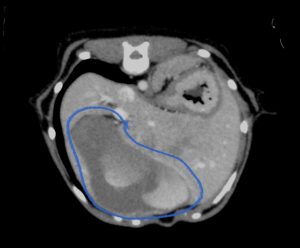

今回治療させていただいたワンちゃんは、数ヶ月前から肝臓(尾状葉乳頭突起)の腫れを指摘されており、CT検査で尾状葉乳頭突起に4センチ大の腫瘤性病変と胃の圧迫、重度の胆嚢拡張を認めました。肝臓腫瘍の初期はほとんど症状がなく(稀に低血糖)、腫瘍が大きくなることで他の臓器を圧迫して症状が出ることが多い印象です。

青線:胆嚢